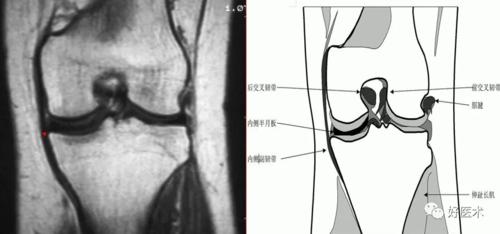

半月板后移征:矢状面上,外侧半月板后 角相对于胫骨外侧平台后移,考虑

横韧带连接内外侧半月板前角,呈现低信号索带样结构 .

膝横韧带3外侧半月板右角偏向内侧,向头侧倾斜,因此在短te时会因魔角

标记:高尔夫球杆形状—外侧层面 标记:不要认为是半月板前角的碎片 矢

半月板桶柄状撕裂矢状面像上半月板体部失去正常的双凹镜形态,前后角